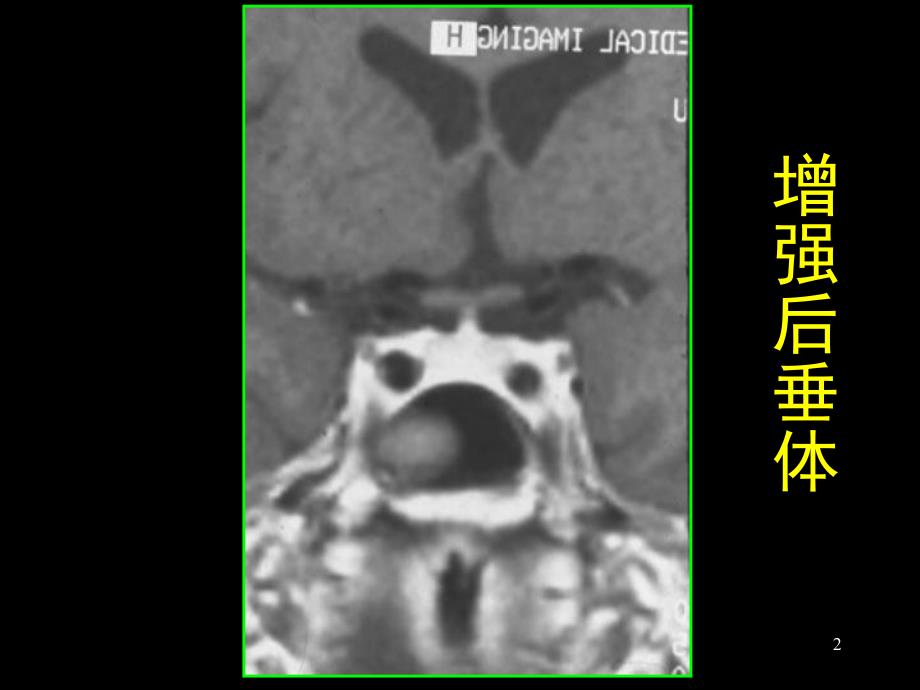

1、1正常垂体2增强后垂体3垂体柄4上缘平坦型5上缘下凹型6上缘上凸型7 鞍上池鞍上池89鞍上池的形态10CT正常垂体11空蝶鞍12蝶鞍扩大的 空蝶鞍13 正常蝶鞍的 空蝶鞍14 垂体发育障碍垂体柄消失、垂体后叶上移15垂体发育障碍垂体柄消失、垂体后叶上移16垂体腺瘤蝶鞍扩大蝶鞍扩大鞍上池鞍上池被肿块占据被肿块占据17垂体瘤18垂体腺瘤19垂体腺瘤20垂体腺瘤21垂体腺瘤(瘤内坏死)(瘤内坏死)22垂体腺瘤(侵犯蝶窦)(侵犯蝶窦)23垂体腺瘤(球形增大)24垂体微腺瘤CT:增强后低密度增强后低密度局限性鞍底凹陷局限性鞍底凹陷垂体柄偏移垂体柄偏移25垂体微腺瘤26垂体微腺瘤增强27垂体微腺瘤28鞍上